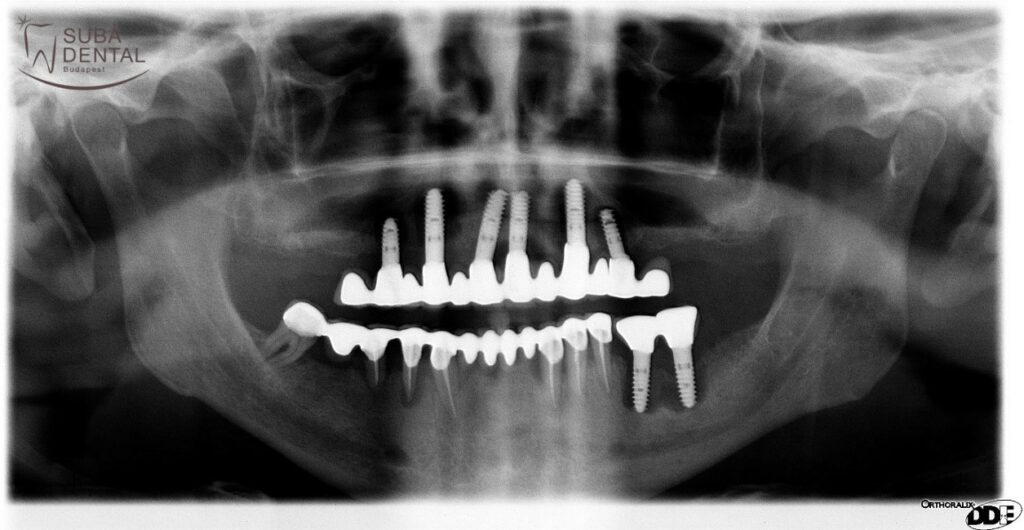

Notre patient qui est un gros fumeur a développé une maladie parodontale sévère. Toutes ses dents ont dû être extraites

Notre patient gros fumeur (qui a évité les examens dentaires et les détartrages pendant des années) a développé une maladie parodontale sévère qui a attaqué non seulement ses propres dents mais aussi les implants posés (inflammation autour de l'implant - périimplantite).

Ces faits ont fondamentalement renversé l'hypothèse précédente selon laquelle, en maintenant une bonne hygiène buccale en plus du tabagisme, nous pouvions parfaitement prévenir les effets nocifs du tabagisme sur les dents. Aujourd'hui, nous savons que même avec les soins bucco-dentaires les plus parfaits et des examens dentaires réguliers, les effets nocifs de la fumée de tabac se produisent! La vraie solution serait d'arrêter de fumer, ce qui serait vraiment important non seulement pour la santé de nos dents, mais pour la santé de tout notre corps (poumons, cœur, cerveau, vaisseaux sanguins). Le tabagisme compromet également le succès à long terme de tous les implants qui pouvaient être implantés! Comme pour les dents, une inflammation peut se développer autour des implants. (Péri-implantite)